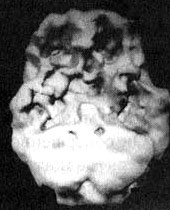

Иллюстрация к книге — Измените свой мозг - изменится и жизнь! [i_091.jpg]

Трехмерное изображение поверхности, вид сверху. Обратите внимание на выраженное улучшение после годового воздержания от алкоголя и наркотиков.